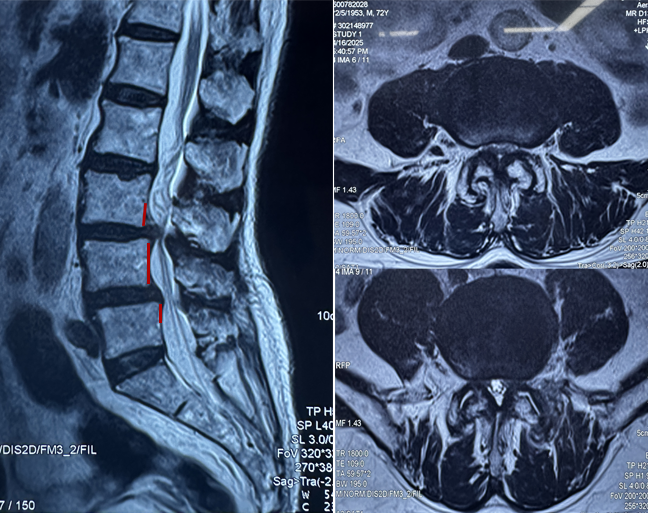

术前核磁:腰3-4、腰4-5椎体滑脱伴腰椎管狭窄

术后核磁:神经受压解除,硬膜囊膨隆